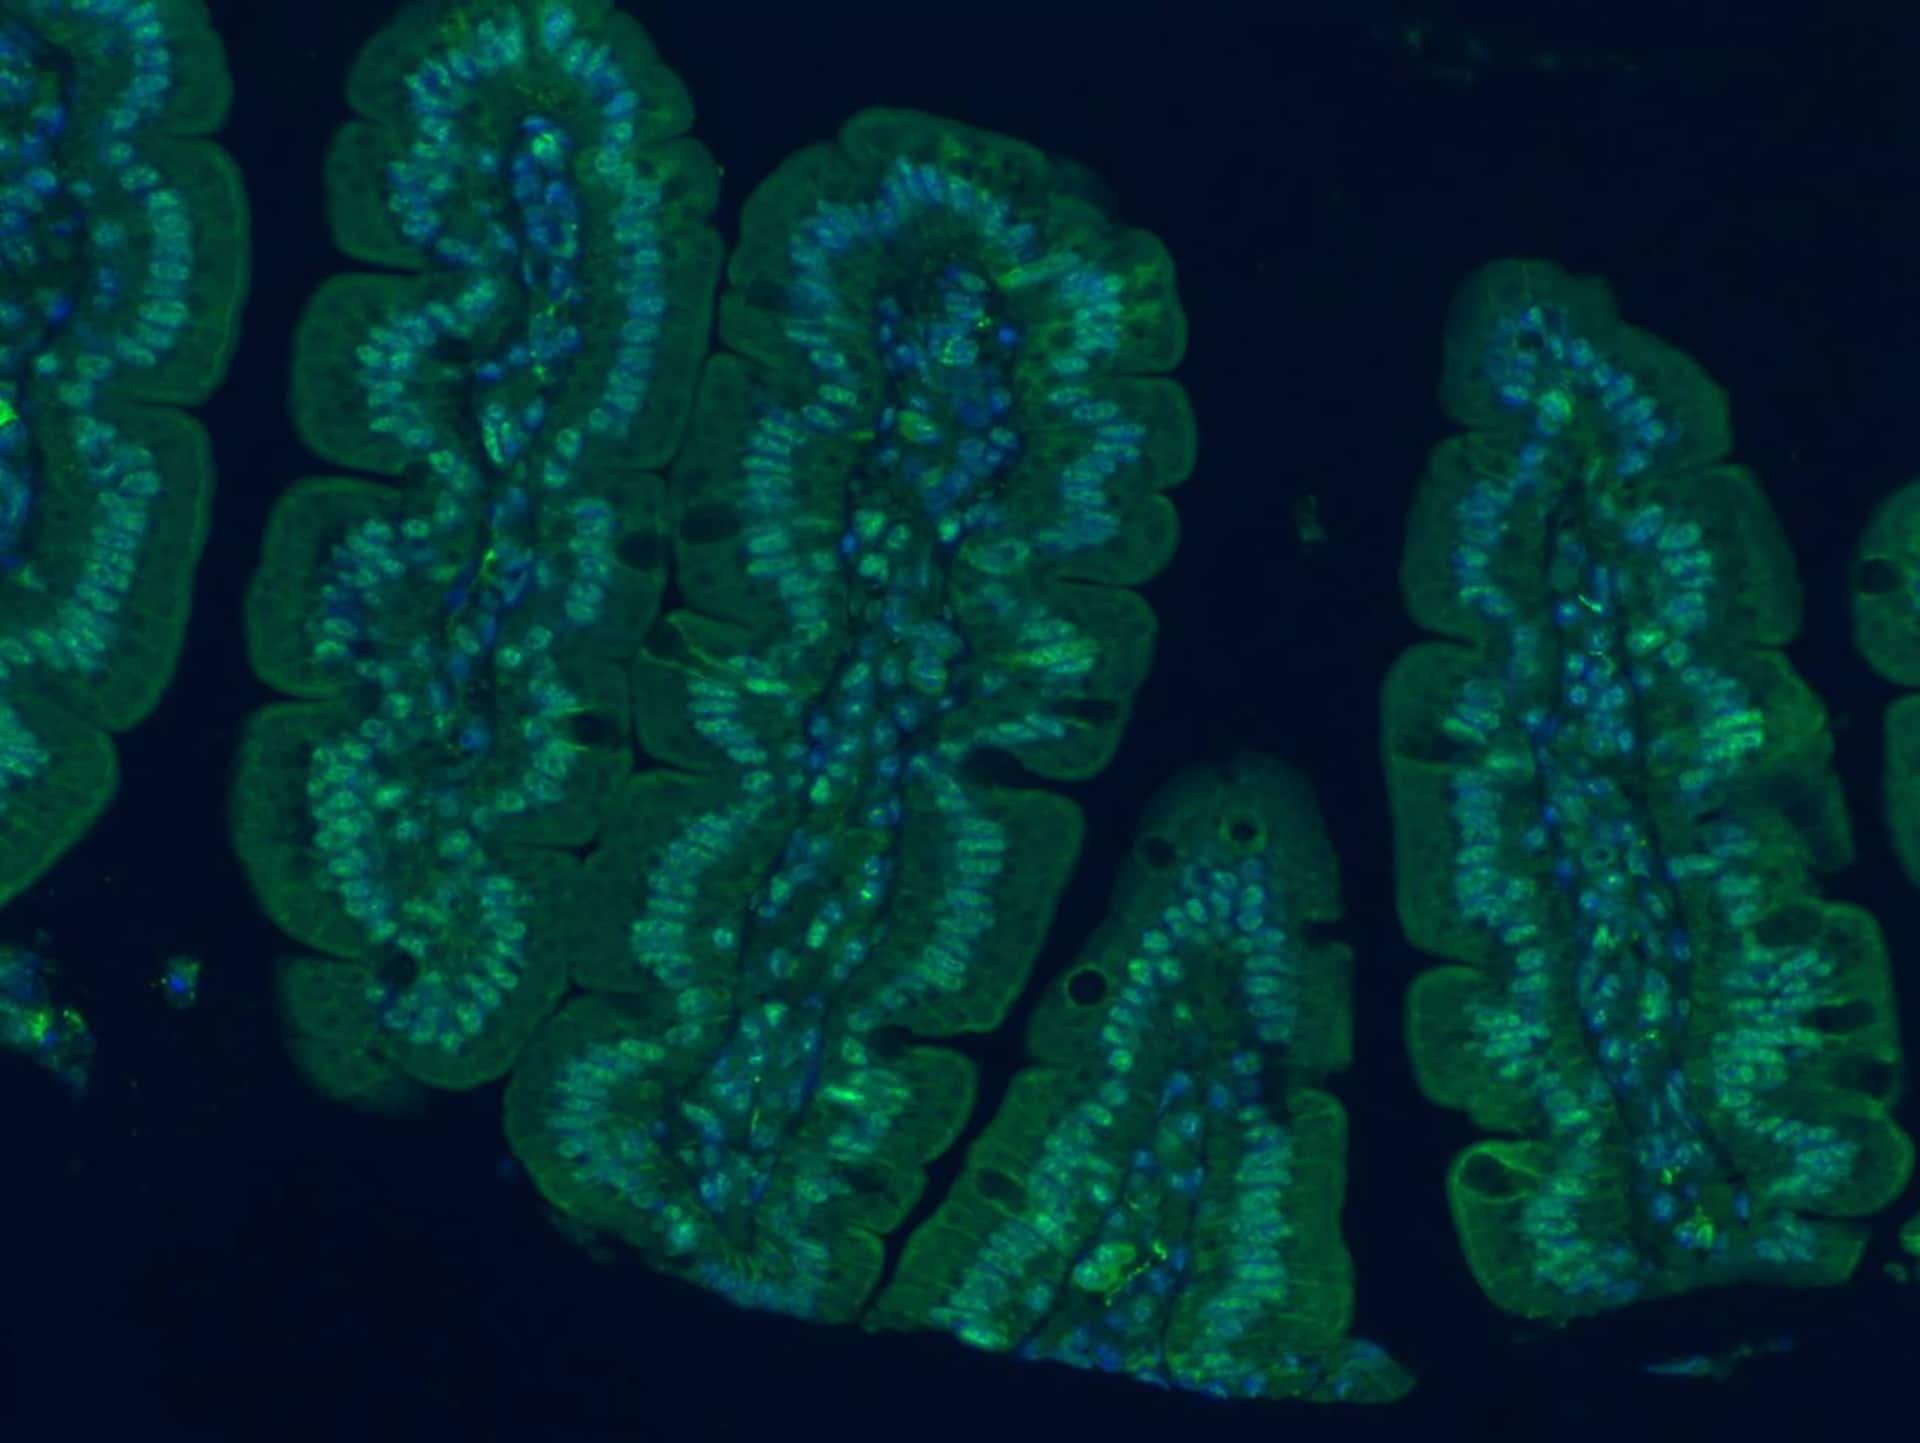

Los investigadores identificaron que la inflamación gastrointestinal y las alteraciones asociadas actúan como un factor directo en el daño cognitivo relacionado con la edad. Descubrieron un camino en tres etapas principales hacia la pérdida de memoria:

-El envejecimiento del tracto gastrointestinal provoca alteraciones en la microbiota intestinal y en el metabolismo.

-Estos cambios son detectados por células mieloides (inmunes) en el intestino, que desencadenan una respuesta inflamatoria.

-Esta inflamación perjudica la conexión entre el intestino y el cerebro a través del nervio vago, reduciendo las señales interoceptivas (sensación interna del cuerpo) que llegan al hipocampo, la región cerebral clave para la formación de memorias y la navegación espacial.

Los autores señalan a la bacteria Parabacteroides goldsteinii como un componente principal. Su abundancia aumenta con la edad y produce metabolitos (ácidos grasos de cadena media) que activan receptores como GPR84 en células mieloides intestinales, generando inflamación. Esta inflamación desactiva las funciones del nervio vago y contribuye al deterioro cognitivo.